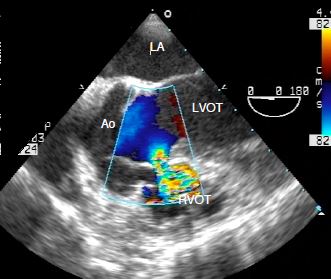

For further information, reference may be made to Chapter 14 (Paediatric cardiac surgery). Illustrations are taken from transesophageal echocardiography (TEE), which anaesthetists may perform in the operating theatre.